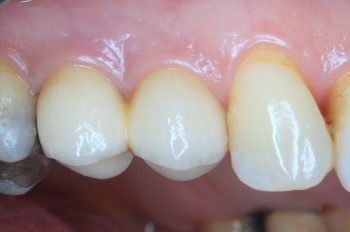

На фото представлены все этапы имплантации зубов от исходного состояния пациента до конечного результата.

Пациентка обратилась с кариесом корня 14 зуба и 15 зуба с разрушением коронковой части зуба, ранее леченного с установкой анкерного штифта.

Имплантация 14, 15 зуба с циркониевой коронкой на импланте: